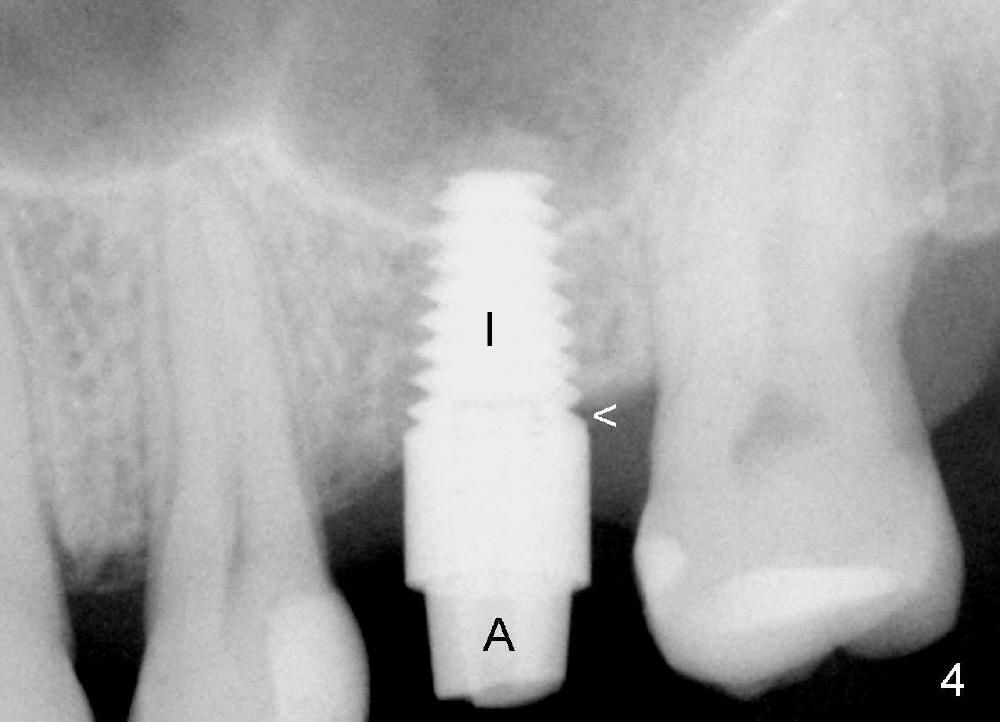

A 48-year-old lady has lost #14 for a while (Fig.1). It looks that bone density at the site of #14 is lower than that mesial to the 2nd premolar. The buccolingual width is wide clinically, although the mesiodistal distance is short (8 mm, Fig.2). A 4-mm tissue punch is used for access. When 1.5 mm pilot drill is used to start osteotomy, it feels that bone density is not low. The first bone expander (2.6 mm) cannot penetrate the bone. Therefore reamers 2.5-3.5 mm are used to increase osteotomy at the depth of 6 mm from the gingival margin. A 4.5x11 mm tap drill is inserted ~ 7 mm with resistance (Fig.3). After 5x11 mm tap, autogenous bone mixed with Osteogen is pushed into the osteotomy and upward. A 5x11 mm implant is placed with > 60 Ncm (Fig.4). After the last X-ray, the implant is torqued 5 more times so that the distal last thread may be able to be fully engaged to the bone. Fig.5 is CT coronal section at the site of #14 5 days postop (B: buccal; L: lingual). Fig.6 is taken 5 months postop with maintenance of sinus lift (*). The crown dislodges 16 months post cementation. In fact the abutment is also loose. The latter is resin bonded, followed by crown cementation (Fig.7). It appears that when the implant is 5 mm or less, the unipost should be permanently cemented in order to prevent crown displacement, particularly for a patient with bruxism and partial edentulism.